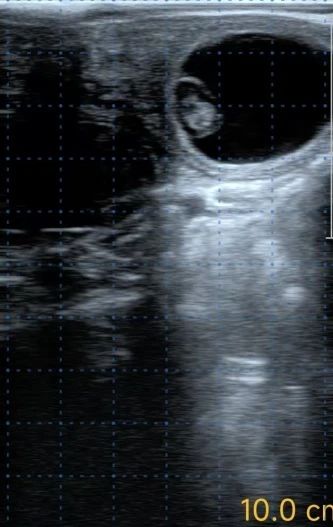

图8 孕检结果成阳性的B超图片

试验组处理母牛161头,孕检呈阳性为111头,妊娠率为68.94%,对照组处理母牛283头,孕检呈阳性为163头,妊娠率为57.6%,试验组妊娠率显著高于对照组。比较不同胎次母牛处理后的受胎率,试验组的妊娠率也都高于对照组,试验结果参见表1。